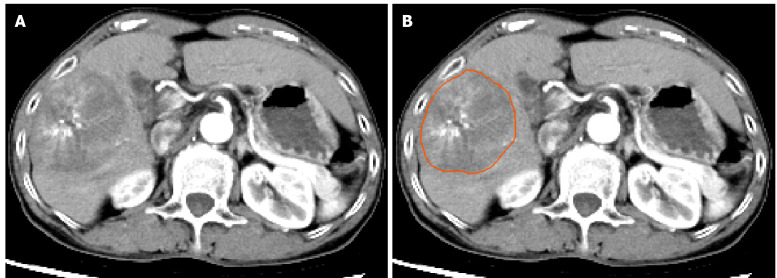

Methods: A retrospective cohort consisting of 192 patients with pathologically confirmed HCC was included, of whom 68 were MVI-positive and 124 were MVI-negative. The patients were randomly assigned to a training set (134 patients) and a validation set (58 patients) in a 7:3 ratio. An additional 45 HCC patients undergoing TACE treatment were included in the TACE validation cohort. A modeling strategy based on computed tomography arterial phase images was implemented, utilizing 2.5D deep learning in combination with a MIL framework for the prediction of MVI in HCC. Moreover, this method was compared with the radiomics signature and clinical signatures, and the predictive performance of the various models was evaluated using receiver operating characteristic curves and decision curve analysis (DCA), with DeLong's test applied to compare the area under the curve (AUC) between models. Kaplan-Meier curves were utilized to analyze differences in recurrence-free survival (RFS) or progression-free survival (PFS) among different HCC treatment cohorts stratified by MIL signature risk.